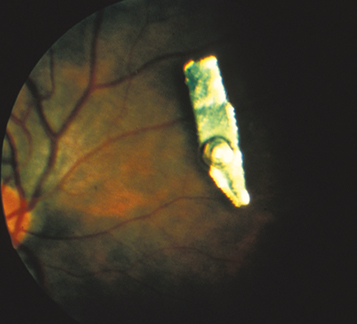

(See Figure 3.11.1.)

May have a clinically detectable corneal or scleral perforation site, hole in the iris, focal lens opacity, or an IOFB. IOFBs are often seen on CT scan (thin cuts), B-scan US, and/or UBM.

See 3.10, Ruptured Globe and Penetrating Ocular Injury. Also, microcystic (epithelial) edema of the peripheral cornea (a clue that a foreign body may be hidden in the AC angle in the same sector of the eye). Long-standing iron-containing IOFBs may cause siderosis, manifesting as anisocoria, heterochromia, corneal endothelial and epithelial deposits, anterior subcapsular cataracts, lens dislocation, retinopathy, and optic atrophy.